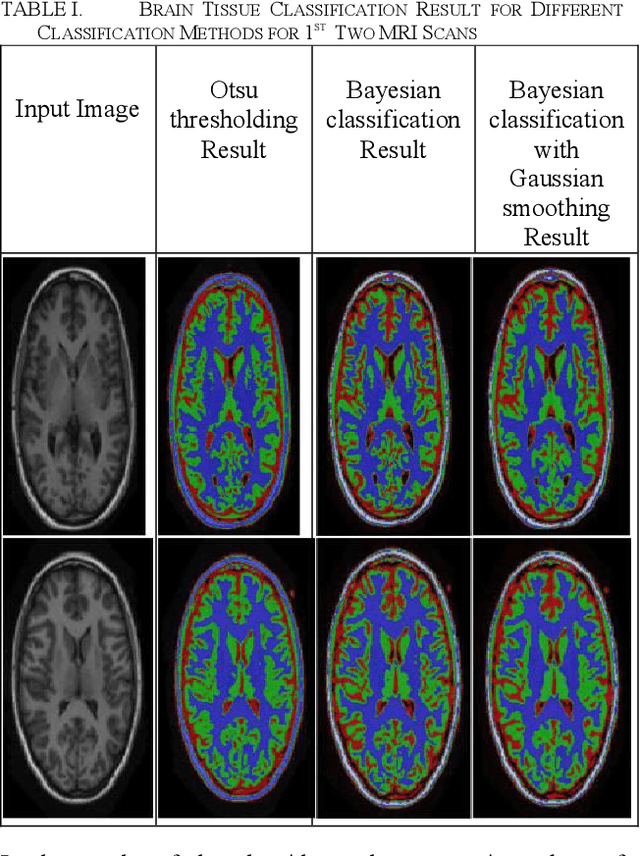

Abstract:Tissue classification is one of the significant tasks in the field of biomedical image analysis. Magnetic Resonance Imaging (MRI) is of great importance in tissue classification especially in the areas of brain tissue classification which is able to recognize anatomical areas of interest such as surgical planning, monitoring therapy, clinical drug trials, image registration, stereotactic neurosurgery, radiotherapy etc. The task of this paper is to implement different unsupervised classification algorithms in ITK and perform tissue classification (white matter, gray matter, cerebrospinal fluid (CSF) and background of the human brain). For this purpose, 5 grayscale head MRI scans are provided. In order of classifying brain tissues, three algorithms are used. These are: Otsu thresholding, Bayesian classification and Bayesian classification with Gaussian smoothing. The obtained classification results are analyzed in the results and discussion section.